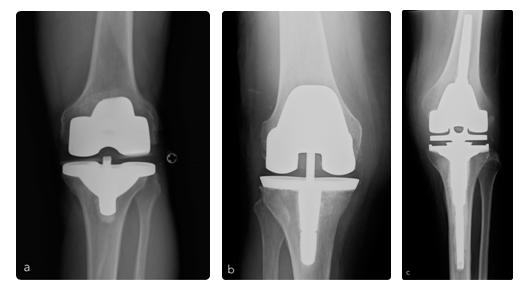

Le ginocchia con gravi deviazioni assiali sono state trattate con protesi con inserti a stabilizzazione posteriore (a), semivincolate (b) o vincolate (c).

Femmina, 54 anni, affetta da gonalgia cronica in ginocchio valgo artrosico (valgismo >30°) (a). La deformità e l'artrosi comportavano una grave impotenza funzionale e dolore con deambulazione consentita per brevi tratti con l'ausilio di un bastone. Il trattamento chirurgico è consistito nella correzione dell'asse del ginocchio e una sostituzione protesica con protesi parzialmente vincolata (b). La paziente in seguito all'intervento è tornata a deambulare senzo bisogno dell'ausilio di bastoni, ed a salire e scendere autonomamente le scale.

Maschio, 57 anni, affetto da gonalgia cronica in ginocchio varo artosico (varismo>30°) (a). La deformità e l'artrosi comportano per il paziente una grave invalidità con difficoltà severa alla deambulazione e all'esecuzione delle normali attività della vita quotidiana. La correzione dell'asse del ginocchio e della artosi è stata ottenuta con l'impianto di una protesi standard (b). Il paziente in seguito all'intervento chirurgico ha ripreso la piena funzione dell'arto operato con scomparsa del dolore.